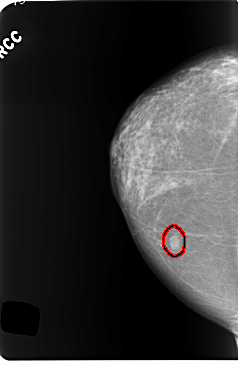

C_0255_1.RIGHT_CC

RIGHT_CC LINES 5832 PIXELS_PER_LINE 3824 BITS_PER_PIXEL 12 RESOLUTION 50 OVERLAY

FILE: C_0255_1.RIGHT_CC.OVERLAY

TOTAL_ABNORMALITIES 1

ABNORMALITY 1

LESION_TYPE MASS SHAPE OVAL MARGINS CIRCUMSCRIBED

ASSESSMENT 4

SUBTLETY 5

PATHOLOGY BENIGN

TOTAL_OUTLINES 1

BOUNDARY